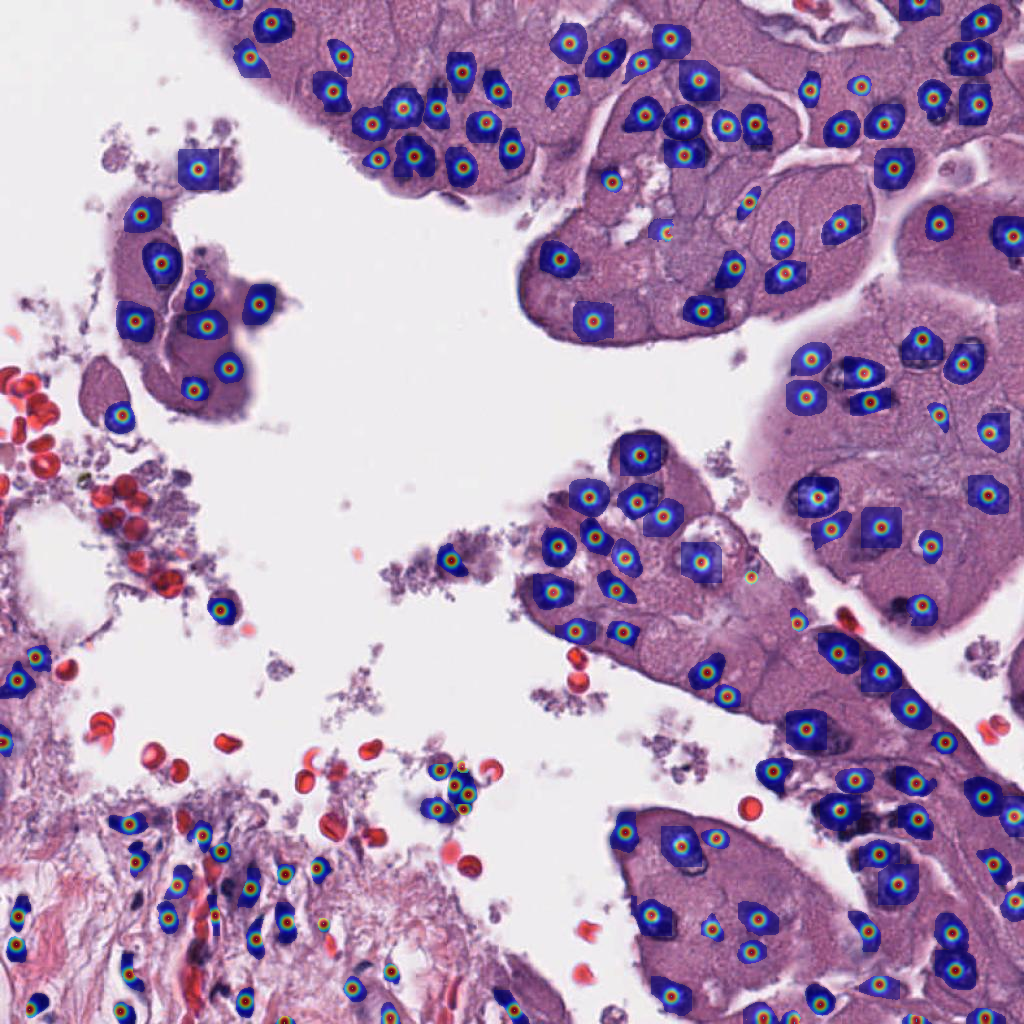

3.6 Cell Detection Postprocessing

For the circle and soft IS ground truth formats we extract cell detection candidates from the segmentation prediction by applying skimage.feature.peak_local_max on the blurred foreground prediction (Figure 3), where:

| (3) |

and are the model predictions for the tumor cell class and background cell class respectively. Only cell candidates with a larger probability for the tumor or background cell class, compared to the background class, are considered. The cell candidate class is assigned as the foreground class with the highest probability. The hard IS requires a different approach, as cell instances are not trained to express a peak at the cell center and tend to overlap. For this reason, markers are extracted from the foreground prediction and then applied in a marker-controlled watershed segmentation to separate touching instance (more details in Appendix 0.B). The cell is assigned a class by majority vote of its pixel class predictions.